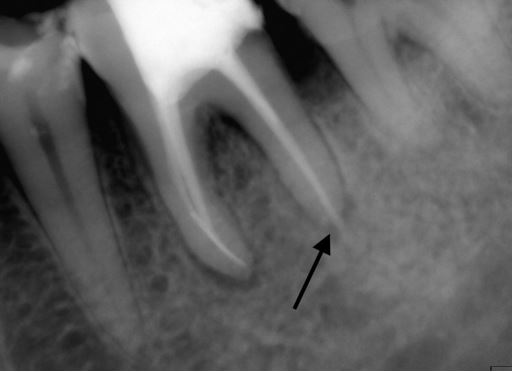

– Sót tủy hoặc sót mảnh vụn tủy (H21.3).